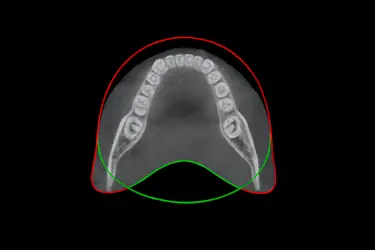

TAC dental , que significa Tomografía Axial Computerizada, es una prueba de imagen diagnóstica destinada a tomar imágenes tridimensionales de los dientes, las estructuras nerviosas y los huesos craneofaciales de una persona.

La principal ventaja de hacerse un TAC dental 3D es que permite a nuestros especialistas realizar cortes bidimensionales y tridimensionales de las imágenes obtenidas de tu boca.

Con las fotos de un TAC dental se pueden ver imágenes detalladas de los dientes, huesos maxilares, mandíbula, raíces dentales y tejidos de alrededor, permitiendo un diagnóstico preciso.

TAC completo de ambas arcadas

Proporciona una imagen 3D completa de las dos arcadas, maxilar superior e inferior, junto con los tejidos y estructuras óseas adyacentes.

Este examen ofrece una visión global de toda la cavidad oral, facilitando la planificación integral de tratamientos que combinan prótesis, ortodoncia o implantes en ambas arcadas.